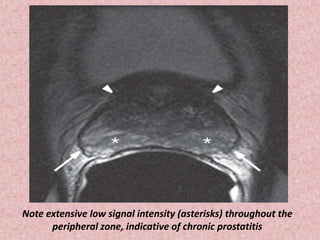

Note extensive low signal intensity (asterisks) throughout the

peripheral zone, indicative of chronic prostatitis

Chronic prostatitis.